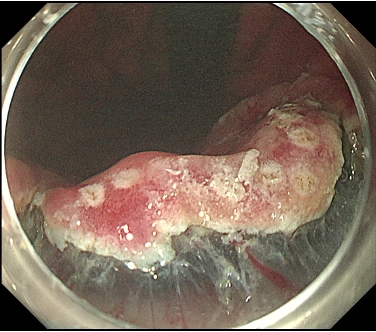

図3: 粘膜切開後に高周波ナイフで粘膜下層を剥離し病変を切除(サンプル)

図3. 粘膜切開を行った後に、高周波ナイフを用いて粘膜の下(粘膜下層)を剥離し病変を切除します。